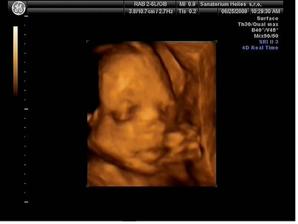

25.6.2009 (24 tt) máme za sebou krásný 3D/4D ultrazvuk v Heliosu. Vše je tak, jak má být :o) A máme definitivně potvrzený pohlaví - je to KLUK - tatínek má důvod k radosti :o) Mimi má 565 g, měří mezi 25 a 30 cm.